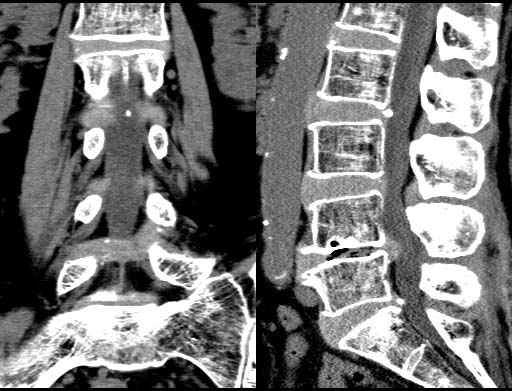

Lumber disc hernia

0.5mmx4, Pitch 3, 60-seconds, 135kV, 130-mAs:

MPR

Recurrent disk hernia at L4/L5 level is beautifully delineated on non-contrast CT. Also note excellent visualization of vacuum phenomenon, calcification of disks, root sleeves and trabecula.